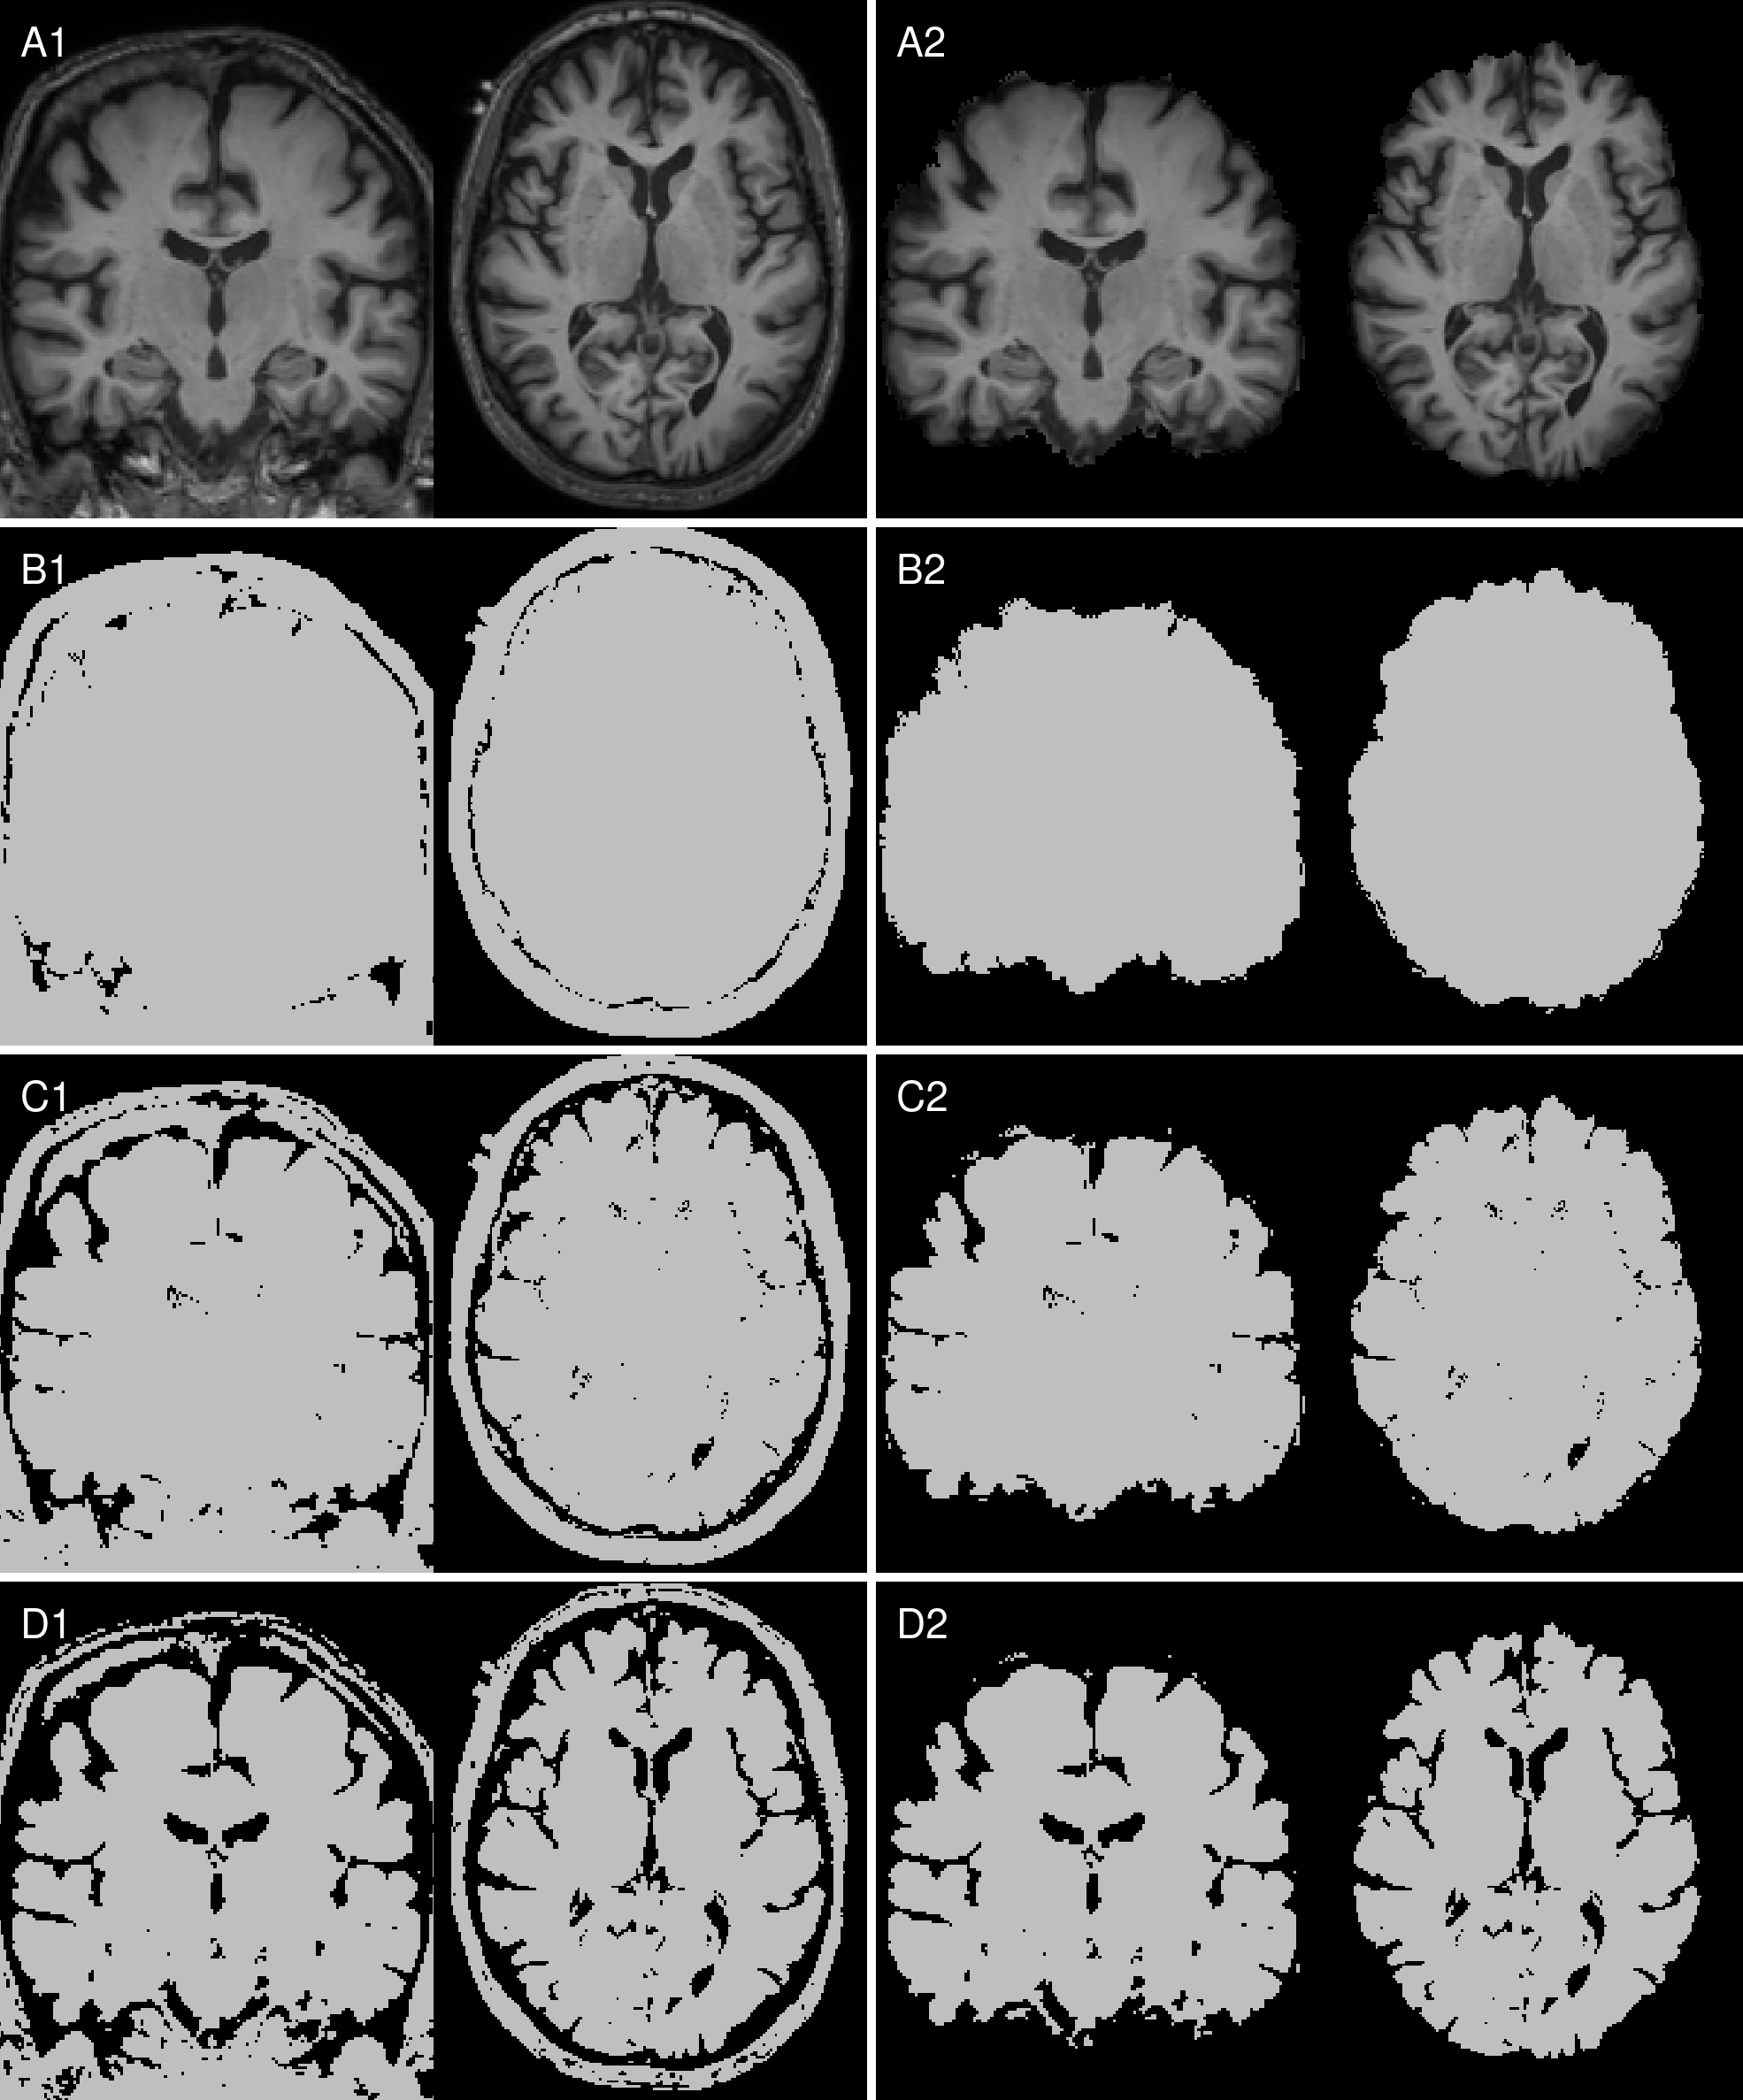

Raw T1w images were reoriented to standard space using FSL-REORIENT2STD [19], cropped to a 160×240×256160\times 240\times 256160 × 240 × 256 matrix size, bias field corrected using N4 [38], and non-linearly registered to the MNI152 template via FSL-FNIRT [19]. Intensity values were normalized to the white matter peak of the brain tissue histogram (196 bins). The outputs of this preprocessing pipeline are referred to as “aligned” images. Individual brain masks were generated in native image space using SIENAX from FSL [34] and warped to the aligned images to create the “skull-stripped” images. Binary masks preserving shape information were derived using manually selected thresholds of 13.75%, 27.5%, and 41.25% of the white matter peak of the brain tissue histogram and the aligned images. These binary masks were also combined with skull-stripped preprocessing, resulting in eight total setups, as illustrated in Figure 1.

Refer to caption

Figure 1: Input image setups: Left column with (A1) aligned T1w MRI, identical binarized T1w images with the manually selected threshold levels (B1) 13.75%, (C1) 27.50% (C1) and (D1) 41.25%, and in the right column the corresponding skull-stripped versions (A2, B2, C2, D2).

We investigated three binarization levels, each aligned with the white matter intensity peak of the image, as depicted in Figure 1. These levels, although chosen arbitrarily, retained differing proportions of anatomical structures, capturing distinct aspects of atrophy, including ventricular enlargement, hippocampal shrinking and cerebellum morphology. As CNNs seem to focus on high-contrast regions [14, 26], these binarization levels allowed us to systematically dissect how different volumetric and structural features influenced model predictions.